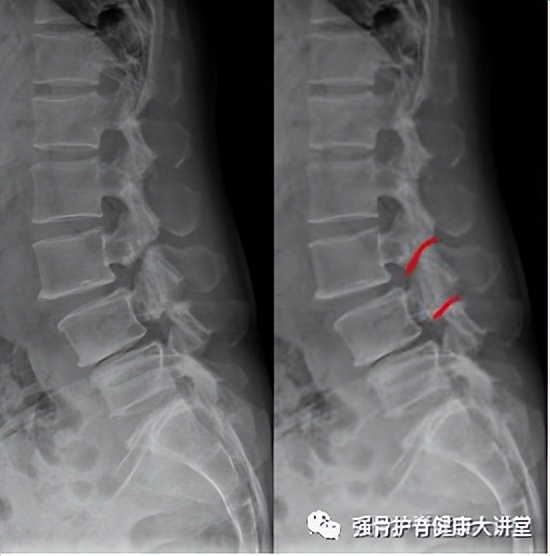

图3

图3为48岁女性,诊断为腰椎峡部裂滑脱(L3-L4),红色线为X线侧位片上峡部裂位置。